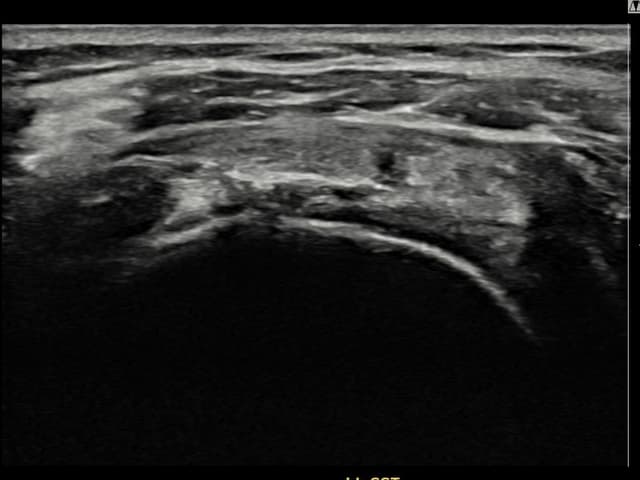

右侧 冈上肌腱 石灰化肌腱炎

14mm × 10mm